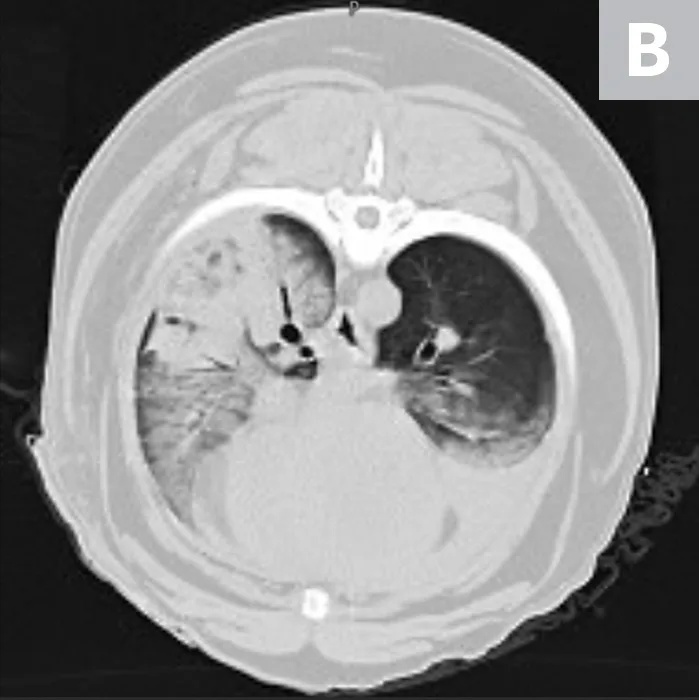

Thoracic CT images of bilateral, diffuse pulmonary infiltrates in a patient with severe trauma secondary to a gunshot wound sustained 24 hours prior to presentation. This patient met 4 criteria for a diagnosis of ARDS (ie, acute onset of respiratory distress, hypoxemia, bilateral diffuse pulmonary infiltrates, known risk factor for trauma).

Evidence of pulmonary capillary leak not due to heart failure or fluid overload (ie, bilateral, diffuse pulmonary infiltrates on thoracic radiographs or CT images)